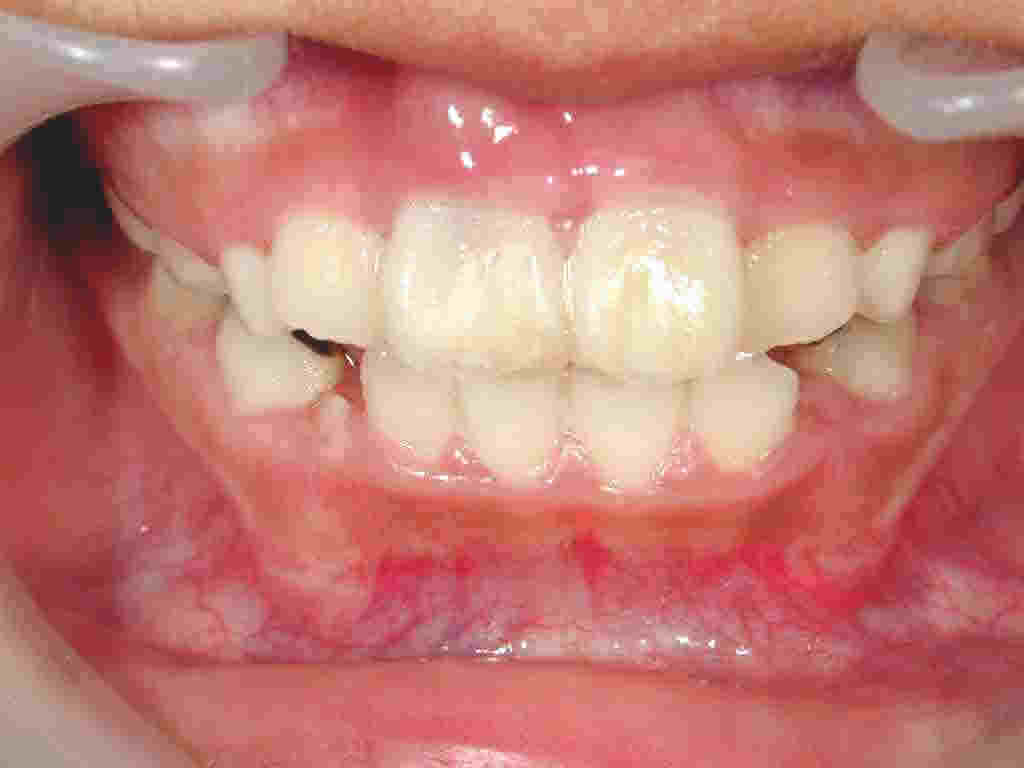

ぶつけて前歯が2本抜けました

抜けた歯の神経の治療をして戻すこともあります。こどもで歯が未完成の場合は血管や神経が再生する可能性が高いので神経は残します。左の症例では神経を抜きました。

左の症例では、骨が折れて唇のすじも裂けていたので7針縫いました。その後、歯と歯肉全体を薄いプラスチックのカバーを作成し保護します。これで骨折した部分は治り食事中も安心です。骨折のため歯の元の位置が不明なので、理想的な位置に歯を固定しました。